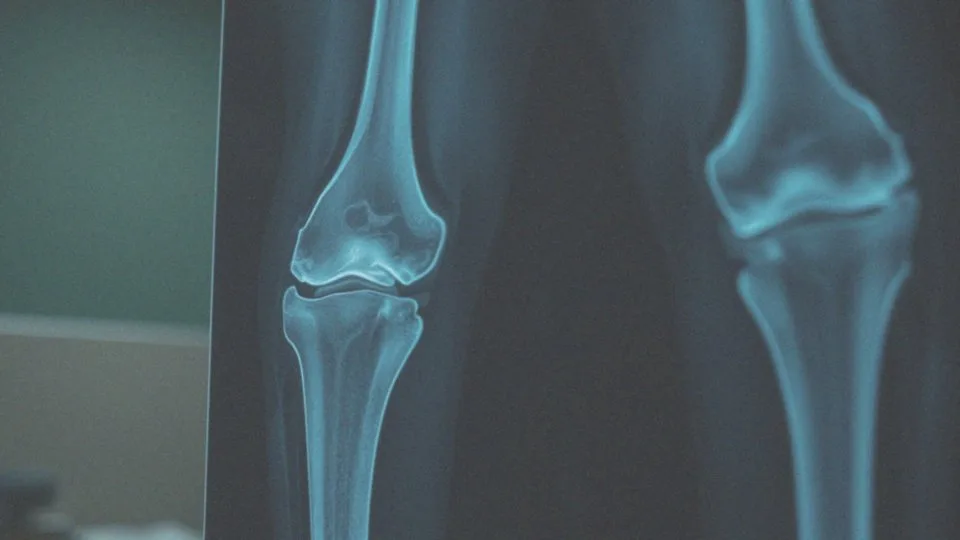

Przed przystąpieniem do usunięcia wyrośli chrzęstno-kostnych konieczne jest przeprowadzenie kilku istotnych badań. Ich głównym celem jest rzetelna analiza zmian oraz ogólnego stanu zdrowia pacjenta. Niezbędne kroki obejmują wykonanie badań obrazowych, takich jak:

- rentgen,

- rezonans magnetyczny (MRI),

- tomografia komputerowa (TK).

Dzięki tym metodom lekarz zyskuje możliwość ustalenia lokalizacji, rozmiaru oraz oddziaływania wyrośli na otaczające tkanki. Co więcej, szczegółowy wywiad lekarski odgrywa kluczową rolę w procesie diagnostycznym. Specjalista analizuje specyfikę schorzenia oraz dotychczasową historię zdrowia pacjenta. Istotne jest zwrócenie uwagi na przewlekłe choroby, które mogą stanowić przeciwwskazanie do zabiegu. Każda osoba powinna być starannie oceniana przed operacją, aby zapewnić jej bezpieczeństwo. W niektórych sytuacjach warto także zasięgnąć porady anestezjologicznej, by upewnić się, że pacjent spełnia wszystkie wymagania dotyczące znieczulenia. Precyzyjna diagnostyka umożliwia podejmowanie świadomych decyzji dotyczących dalszego postępowania terapeutycznego. Taki proces zwiększa nie tylko bezpieczeństwo operacji, ale również jej skuteczność. Staranna ocena stanu zdrowia pozwala na efektywne usunięcie wyrośli oraz na zminimalizowanie ryzyka powikłań, co przyspiesza powrót pacjenta do zdrowia po zabiegu.

W diagnostyce wyrośli chrzęstno-kostnych stosuje się kilka istotnych metod, które pomagają w ocenie tych zmian. Pierwszym krokiem są różnorodne badania obrazowe. Wśród nich można wymienić:

- tomografię komputerową (TK).

Te techniki umożliwiają wizualizację wyrośli oraz analizę ich lokalizacji, wymiarów i wpływu na okoliczne tkanki. Rentgen dostarcza ogólnych informacji dotyczących struktury kostnej, natomiast MRI i TK oferują znacznie dokładniejszy obraz, niezbędny do oceny charakterystyki zmian. Dzięki takim badaniom lekarze mogą zdecydować, czy konieczne będzie przeprowadzenie interwencji chirurgicznej.